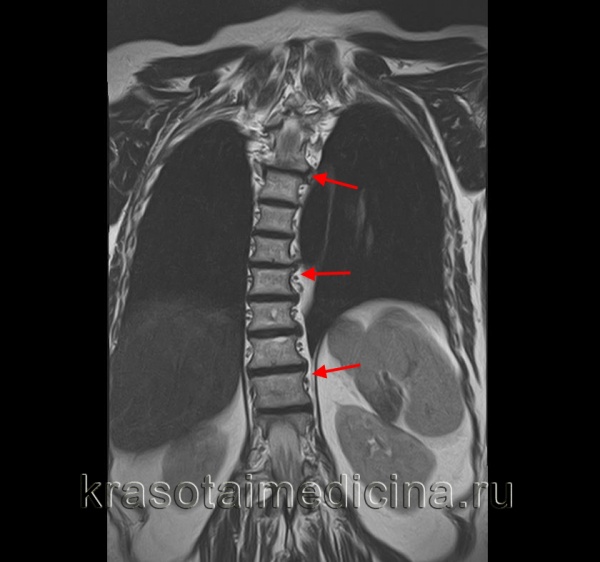

КТ ОГК. Тяжелая левосторонняя сколиотическая деформация грудопоясничного перехода.